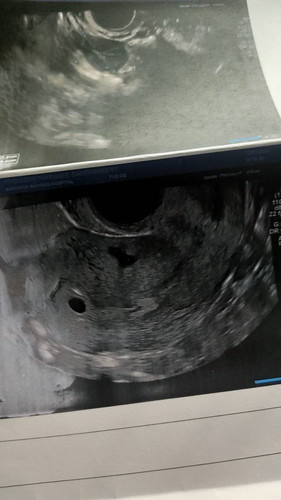

ขอสอบถามแม่ๆๆคะ ตอนนี้ท้องได้ 4 สัปดาห์ แล้ววันนี้ มีอาการเลือดออก นิดนึง เลยไปพบคุณหมอ อัลตร้าซาวด์

หมอฉีดยากันแท้งมา แล้วอีกวันหลังฉีดยากันแท้ง ยังมีเลือดออกเป็นสีน้ำตาลนิดหน่อย น้องยังปกติอยู่มั๊ยคะ